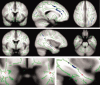

The pattern of degenerative changes in the brain white matter (WM) in aging, mild cognitive impairment (MCI), and Alzheimer's disease (AD) has been under debate. Methods of image analysis are an important factor affecting the outcomes of various studies. Here we used diffusion tensor imaging (DTI) to obtain fractional anisotropy (FA) measures of the WM in healthy young (n = 8), healthy elderly (n = 22), MCI (n = 8), and AD patients (n = 16). We then applied "tract-based spatial statistics" (TBSS) to study the effects of aging, MCI, and AD on WM integrity. Our results show that changes in WM integrity (that is, decreases in FA) are different between healthy aging and AD: in healthy older subjects compared with healthy young subjects decreased FA was primarily observed in frontal, parietal, and subcortical areas whereas in AD, compared with healthy older subjects, decreased FA was only observed in the left anterior temporal lobe. This different pattern of decreased anatomical connectivity in normal aging and AD suggests that AD is not merely accelerated aging.